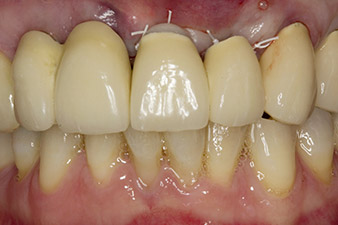

Situación después del implante y del aumento

Imagen 6: Situación después del implante y del aumento: el puente antiguo se volvió a colocar como solución provisional para la fase de cicatrización, con el elemento del puente pulido en la posición de implante 22. Como sustituto definitivo se programó un puente de óxido de circonio desde la posición 12 hasta el implante que aún debía insertarse en la posición 23.